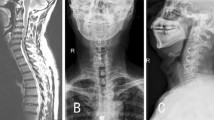

A total of 63 consecutive patients with cervical degenerative disc disease who underwent ACDF using either the zero-profile anchored spacer or the stand-alone cages and a titanium plate fixation between April 2011 and April 2013 were enrolled in this retrospective study. They were divided into two groups based on surgical procedure. 30 patients who underwent fusion using zero-profile anchored spacer (ROI-C, LDR, Troyes, France) implants were classified as anchored group (Fig. 1), and 33 patients underwent fusion using stand-alone cages and an anterior plate (Medtronic, Minneapolis, American) served as the non-anchored group (Fig. 2). The average age was 56.8 ± 11.0 years (range 37–77 years) in the anchored group and 54.0 ± 10.0 years (range 34–72 years) in the non-anchored group. The inclusion criteria were: (1) myelopathy or radiculopathy on the physical examination; (2) spinal cord or root compression visible on recent magnetic resonance imaging (MRI) at one disc level or two disc levels; and (3) no response to at least 6 weeks of conservative treatment. Exclusion criteria were: (1) significant segmental instability and developmental stenosis; (2) a history of cervical spine surgery and other cervical diseases, including ossification of the posterior longitudinal ligament, fracture, tumor, infection, or severe osteoporosis; and (3) a requirement for simultaneous anterior and posterior surgery. The patients’ preoperative data and number of treated segments are shown in Table 1. There were no statistically significant differences for patient age, sex, number of treated segments, follow-up time, or hospital stay between the anchored group and the non-anchored group (P > 0.05, Table 1). This study was approved by the Institutional Ethics Committee of Soochow University.

All patients were followed up for at least 12 months with the mean follow-up period of 24.0 ± 7.9 (range 12–36) months. All devices were implanted successfully, and there were no hematoma, deep infection, bolt loosening or rupture of anchoring clips, screws or titanium plates observed in two groups during follow-up period. The zero-profile anchored spacers were implanted in 31 patients (46 segments). The non-anchored group consisted of 43 patients (48 segments) treated with stand-alone cages and a titanium plate. Surgical procedures covered the whole extent of the subaxial cervical spine from C3 to C7. Patient characteristics were very similar among the two treatment groups (Fig. 3). Anchored group had a mean intraoperative blood loss of 56.8 ± 19.0 ml in single-level and 78.8 ± 22.5 ml in two-level while the average operative time was 80.4 ± 12.1 min in single-level and 124.3 ± 19.3 min in two-level. Non-anchored group had a mean intraoperative blood loss of 89.4 ± 29.7 ml in single-level and 102.3 ± 36.6 ml in two-level while the average operative time was 108.7 ± 22.8 min in single-level and 143.3 ± 22.4 min in two-level. The differences between the operative time and intraoperative blood loss for the anchored group and non-anchored group were statistically significant (P < 0.05, Table 3). There were no statistically significant differences for postoperative JOA scores, NDI scores and cervical lordosis between the anchored group and the non-anchored group (P > 0.05). None of patient complained about dysphagia before operation. The postoperative JOA scores and NDI scores in both groups differed significantly from their respective preoperative JOA scores and NDI scores (P < 0.001, Table 4). The JOA recovery rate was 61.3 ± 11.4 % in the anchored group and 59.7 ± 15.6 % in the non-anchored group. There were no significant differences in the JOA recovery rate between two groups. Six (20.0 %) patients complained about mild dysphagia at postoperative 2 weeks in the anchored group; the dysphasia disappeared at postoperative 3 months. There were 14 (42.4 %) patients who complained of dysphagia in the non-anchored group. Eight patients complained about mild dysphagia and six patients complained of moderate dysphagia at postoperative 2 weeks. After conservative treatment, five patients had recovered at postoperative 3 months, but nine patients had no apparent relief at the last follow-up. There were no significant difference in the presence of dysphagia between the two groups at postoperative 2 weeks, but significant difference in incidence of dysphagia at postoperative 3 months was found (P < 0.001, Table 5). The postoperative cervical lordosis in both groups differed significantly from their respective preoperative cervical lordosis (P < 0.001, Table 4). But no significant difference was found between the two groups at each time point (P > 0.05). Solid fusion was achieved in all patients of two groups at 3–6 months postoperatively (Fig. 4). There were no adjacent disc degeneration and instability observed in two groups.